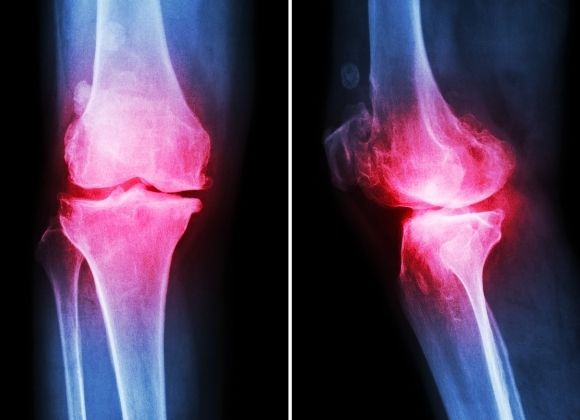

• Artróza

Artróza

Jeden z nejvíce patrných dopadů obezity na tělo je zvýšené opotřebení kloubů, především ve spodních končetinách. Typické jsou problémy s koleny, kotníky a kyčlemi, které jsou zvýšenou vahou vystavovány většímu tlaku, což může vést až k artróze. K problémům s klouby se může přidat také dna, způsobující velké bolesti kloubů.